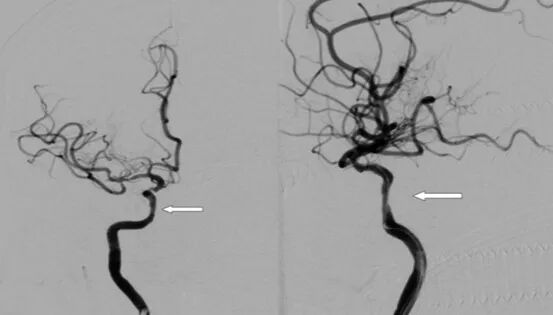

全脑及病变处不同体位造影。

导丝怎么扩【载药时代 球扩天下】NOVA DES®颅内药物洗脱支架在颈内动脉颅内段重度狭窄中的应用体会二例!_https://www.jmylbn.com_新闻资讯_第13张

导丝怎么扩【载药时代 球扩天下】NOVA DES®颅内药物洗脱支架在颈内动脉颅内段重度狭窄中的应用体会二例!_https://www.jmylbn.com_新闻资讯_第14张

导丝怎么扩【载药时代 球扩天下】NOVA DES®颅内药物洗脱支架在颈内动脉颅内段重度狭窄中的应用体会二例!_https://www.jmylbn.com_新闻资讯_第20张

导丝怎么扩【载药时代 球扩天下】NOVA DES®颅内药物洗脱支架在颈内动脉颅内段重度狭窄中的应用体会二例!_https://www.jmylbn.com_新闻资讯_第21张

重要影像结论:右侧颈内动脉C4段重度狭窄;右侧颈内动脉C6段中度狭窄;左侧颈内动脉C5段中度狭窄;左侧大脑前动脉A1段重度狭窄。